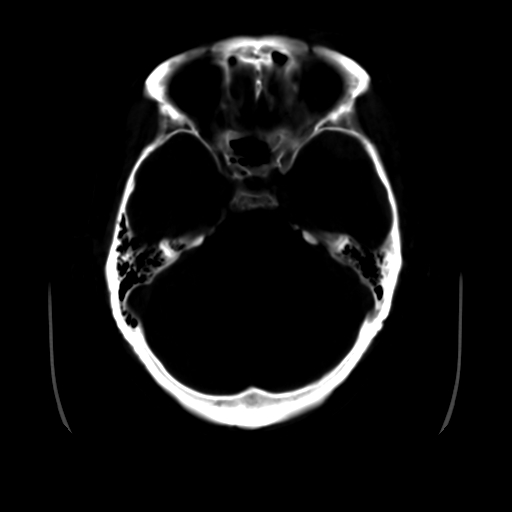

男,51岁,头外伤一小时,呕吐两次。

1)左侧中颅窝蝶骨翼后方硬膜外血肿。2)左侧颞顶部硬膜下血肿。3)蛛网膜下腔出血。4)左侧筛窦及双侧蝶窦炎症(或积血)。5)左侧额部头皮软组织肿胀。